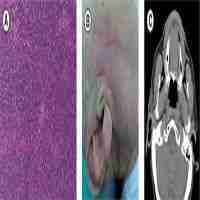

| Description | Journal: Cancer Biology & Therapy Merkel cell carcinoma (MCC) is a rare and aggressive neuroendocrine skin cancer. Until recently, no durable treatment options were available for patients with advanced disease. As an immunogenic cancer, MCC was hypothesized to be a candidate for PD-L1/PD-1 targeted therapy. On March 23, 2017 the US Food and Drug Administration granted accelerated approval for avelumab, an anti-PD-L1 monoclonal antibody, for the treatment of metastatic MCC on the basis of the JAVELIN Merkel 200 trial. Here we examine the results and implications of this pivotal study, published in Lancet Oncology by Kaufman et al., as well as current developments in the use of immune-checkpoint therapies for treating patients with MCC. |